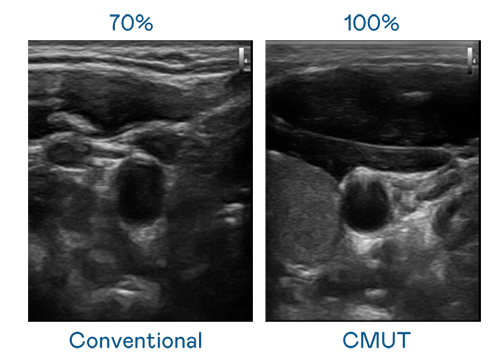

CMUT 技术是一种用电容式微机电元件来产生超音波讯号的技术。与传统 PZT 压电式技术相比,CMUT 频宽增加 30%,更宽频的超音波讯号让影像解析度大幅提升,是实现高影像品质医疗超音波扫描、促进精准医疗发展的关键技术。

超音波影像的解析度高低,首先取决于探头能发出的讯号频宽。男儿无罪 CMUT 可提供高清晰的超音波讯号,提供高频宽、高灵敏度、影像纹理细节更高的超音波影像,协助医护人员缩短影像判读时间及利用精准的医疗影像进行诊断。